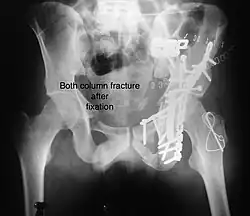

Combined both column fractures These are the most complex injuries. Here the weight bearing roof or dome of the acetabulum is a floating piece. This adds to complexity of management.

Treatment

Like any other acetabular fracture, if the femoral head is dislocated out of the socket, early reduction into socket is a priority. However, in this injury, non-operative treatment rarely gives satisfactory results. Surgical management is ideal. The choice of approach rests with the surgeon, but going from front, or anterior approach is must. The posterior injury may be tacked with anterior approach by experienced surgeon. If the patient is unfit to undergo major surgery due to any reason, longitudinal traction to achieve secondary congruence of hip may help to restore hip function, though partially.